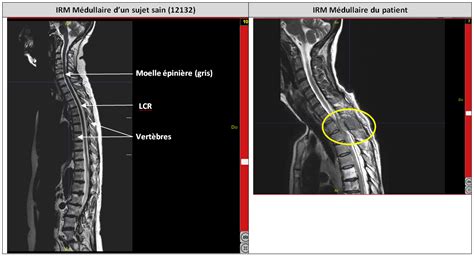

Le diagnostic radiologique de l'ischémie médullaire repose principalement sur l'imagerie par résonance magnétique (IRM) médullaire. Cependant, cet examen n'est pas toujours aisé, notamment en raison du délai d'apparition des anomalies et des diagnostics différentiels à éliminer.

- IRM Médullaire : L'IRM est l'examen de référence et doit être réalisée en urgence, idéalement dans les 6 heures suivant l'apparition des symptômes. Les séquences pondérées en T2 sont essentielles pour visualiser les lésions ischémiques sous forme d'hypersignaux. Néanmoins, il est important de savoir que ces anomalies peuvent être absentes ou discrètes dans les 12 à 24 heures suivant l'apparition des symptômes. Dans ces cas, un contrôle IRM 24 à 48 heures après le premier examen peut être nécessaire pour confirmer le diagnostic. L'aspect classique en IRM T2 est un hypersignal centromédullaire, bilatéral et symétrique, correspondant au territoire de l'artère spinale antérieure, parfois décrit comme un signe en "œil de hibou" ou "œil de serpent" sur les coupes axiales. Des hypersignaux postérieurs signent une atteinte du territoire spinal postérieur.